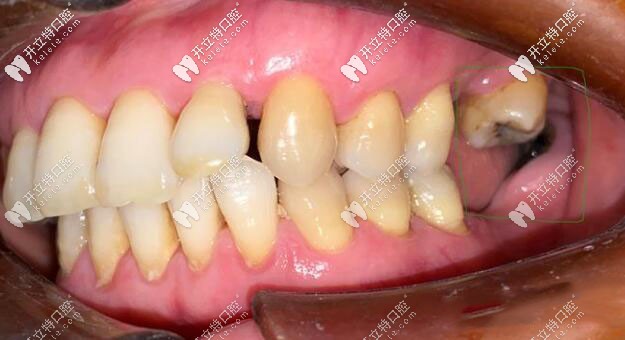

右下就比較簡單,就是缺兩顆種兩顆;但左邊的情況就比較復雜,不僅有殘根齲壞的智齒,但是后面的骨頭還算是好的,醫(yī)生的建議是上下各種兩顆,但是用三顆牙冠修復。